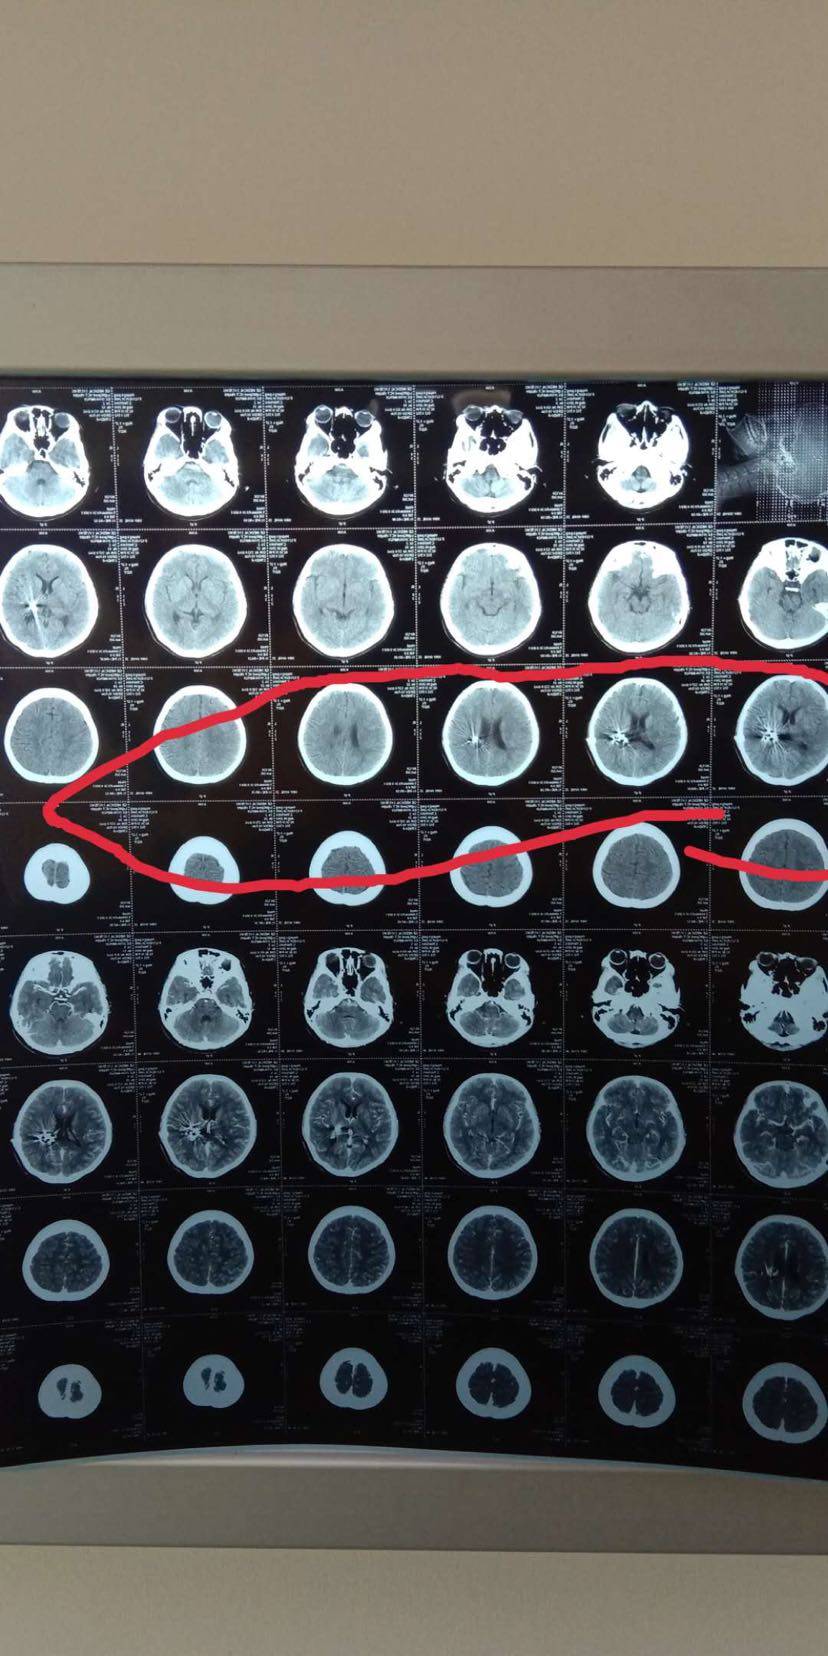

第二步:用放射性碘125粒子,通过三维立体成像技术(3D影像),铺助3D建模精准植入到肿瘤内部,在内部持续杀死肿瘤,不伤害正常细胞。

有人说粒子植入是否适合肺、肝、脑、淋巴或者其他组织?这取决于医生的临床试验。